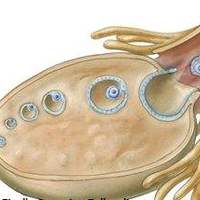

2. 子宫内膜筹备:

通过雌激素调护内膜厚薄程度至8-12mm,并监测血行信号。传统医学辅助方案如针灸可提高内膜容受性,临床数据显现着床率提高约15%。